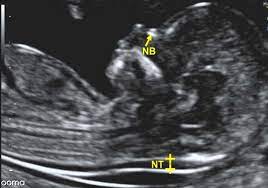

- اولتراسوند سطح دو جنین

- انجام سونوگرافی غربالگری

- سونوگرافی داپلرهای جنین و مادری